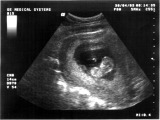

Hier zeig ich euch mal meinen Dickkopf(hab ich übrigens von meiner Mami)Naja, was ich so von meinen Papa mitgekriegt habe, ist der ja auch nicht ohne. Ich bin jetzt 15 Wochen alt.

Das Bild entstand am 28.05.03